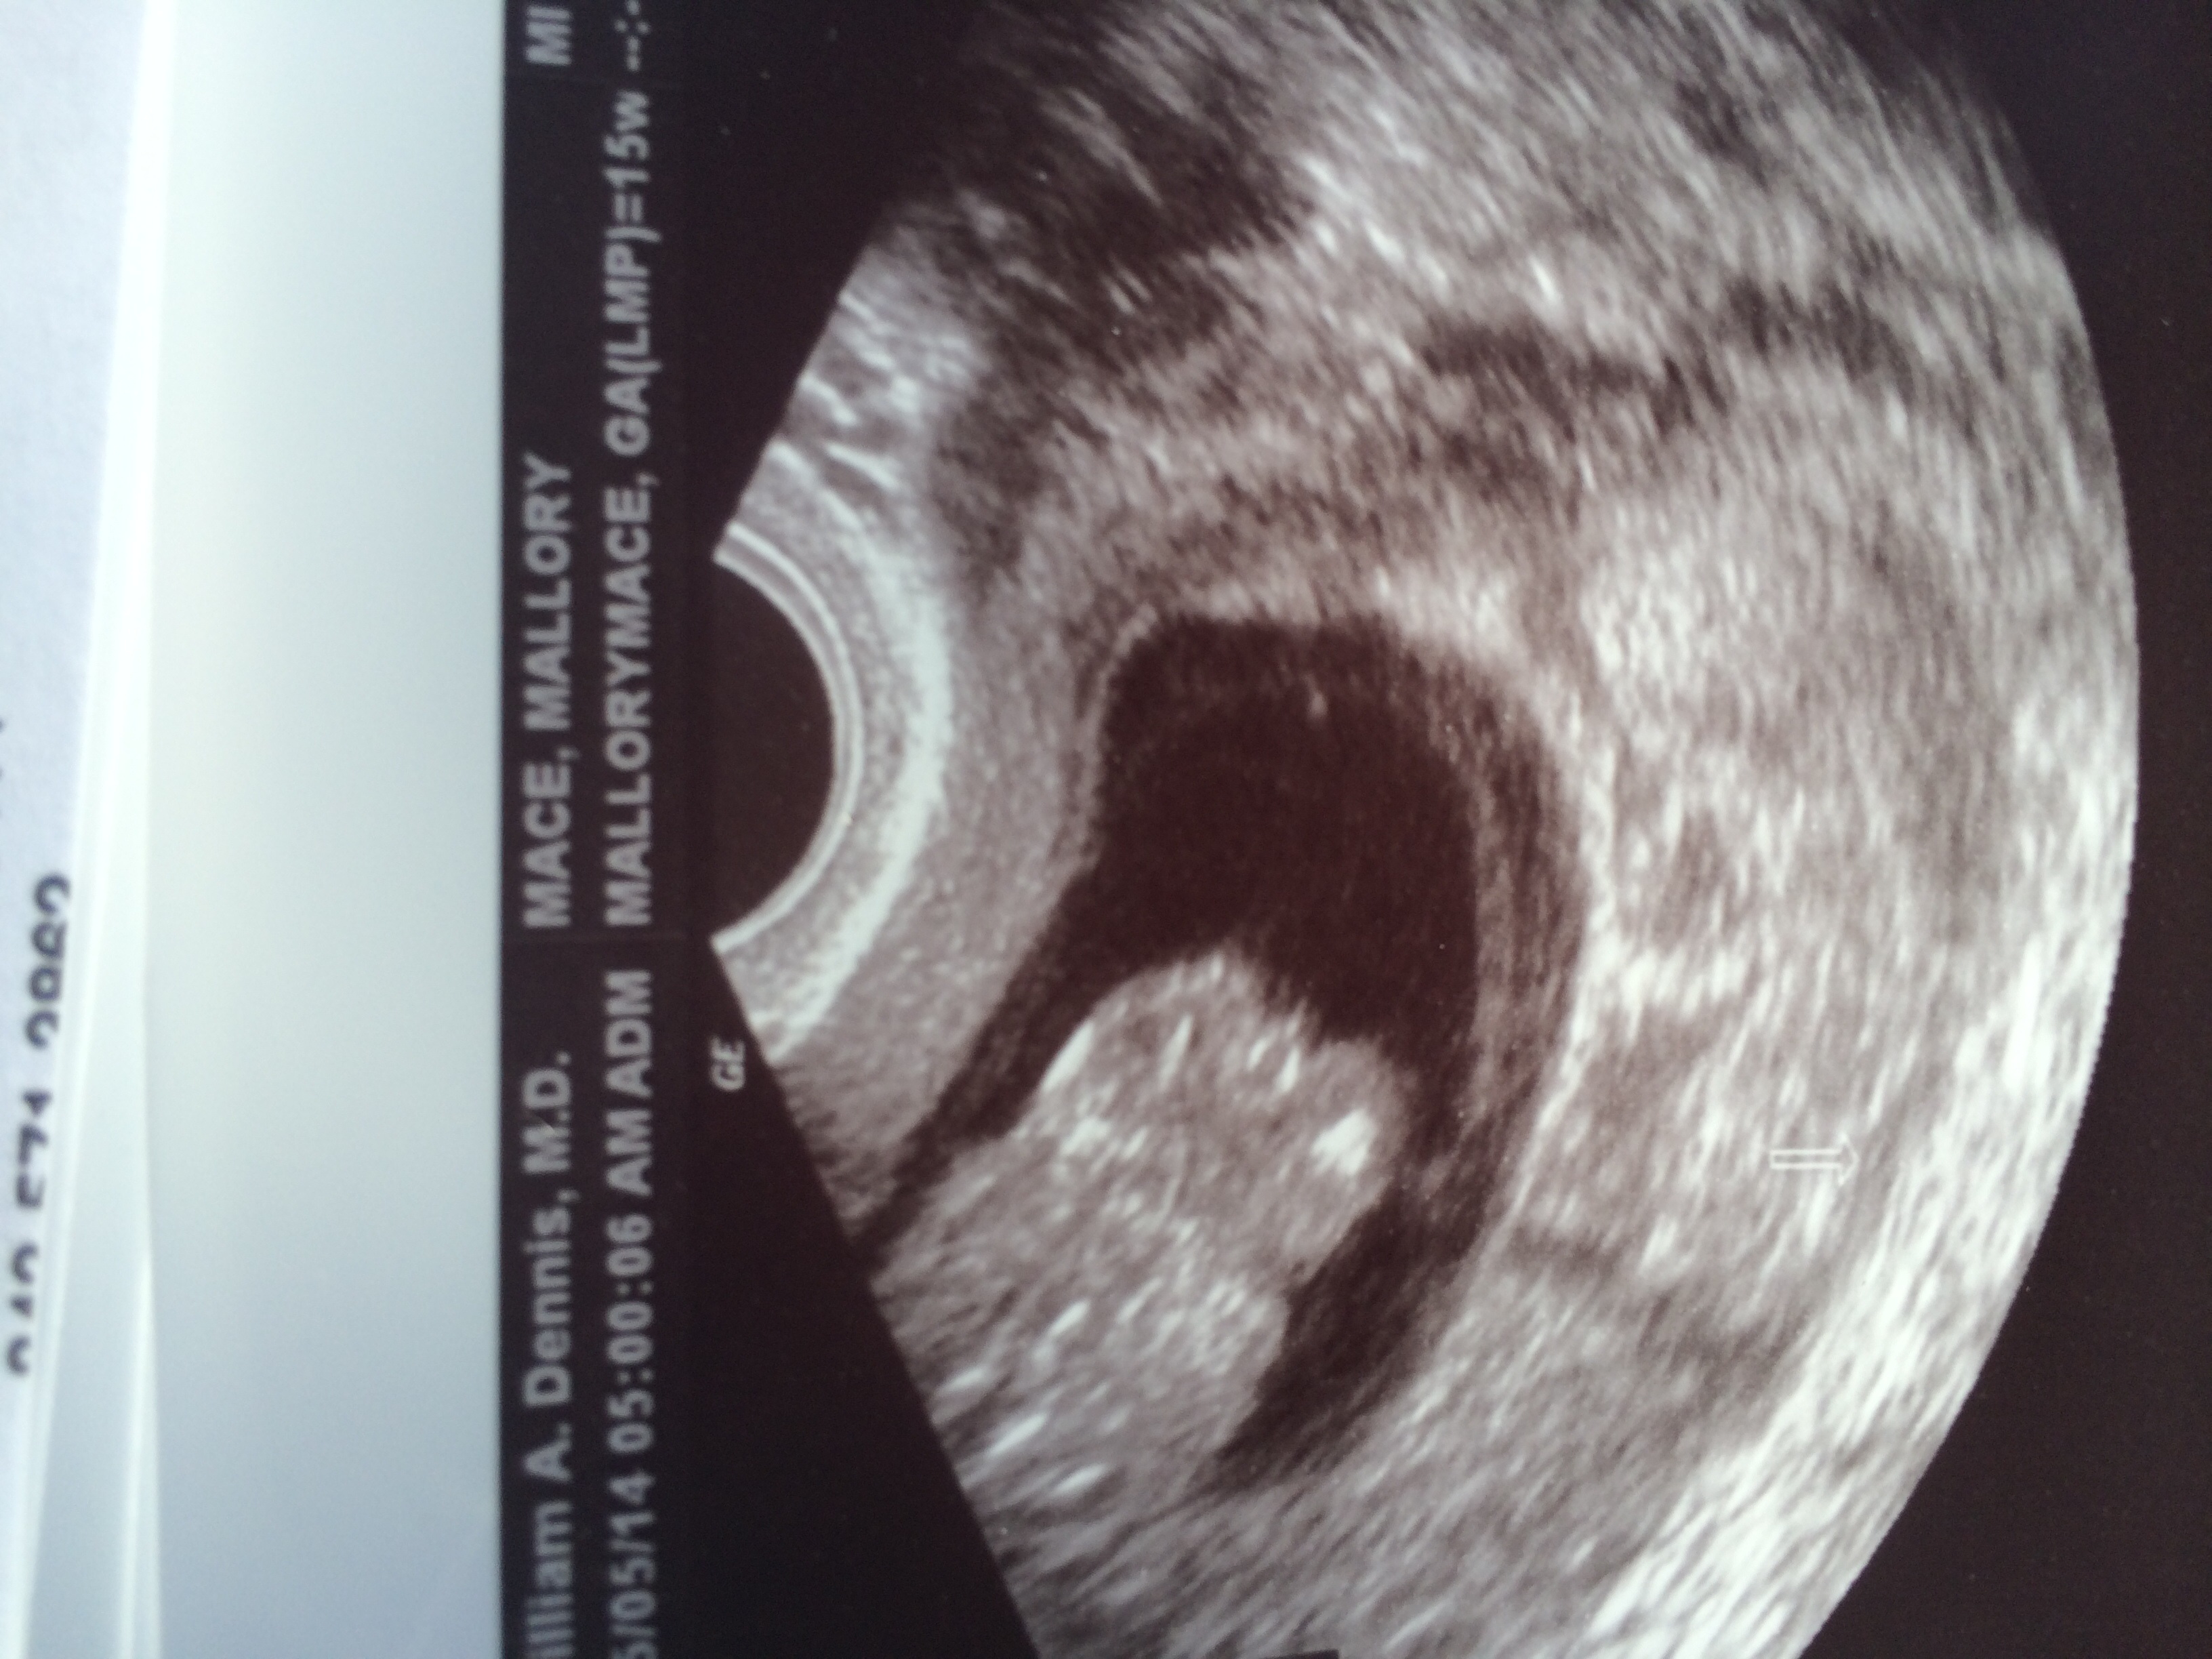

My baby was flipping around like crazy at my 13+2 week ultrasound. My doctor guessed boy. I'm not sure if this is butt cheeks or if the legs are tucked up to the belly, but there is definitely something between there! We didn't get any clear shots of baby laying on back for the "nub" theory, but I'm passed 12 weeks so I'm not sure if the nub still applies. What do y'all think?? Boy or girl?